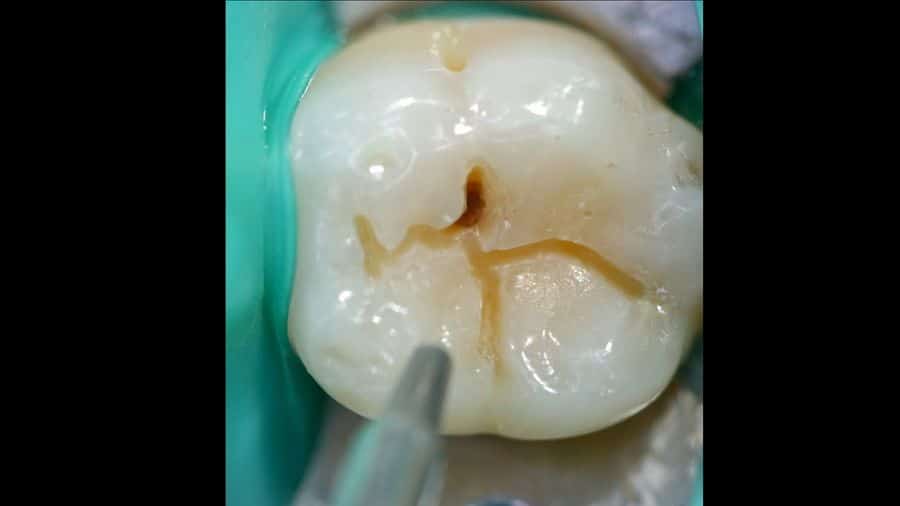

Air abrasion. Minimally invasive tooth decay treatment

Dental air abrasion is a minimally invasive method of treating caries, with no discomfort, vibrations or high-pitched sounds

The air abrasion treatment system consists of using a spray of 30 – 80 micron aluminium oxide particles to eliminate the caries tissue without the need for a burr (the classic drill with the high-pitched sound). The instrument does not touch the tooth, only the spray does, and so the vibration is barely noticeable.

Furthermore, the use of air abrasion means we can cure even extremely small caries. It is a minimally invasive method for treating caries. The combination of early detection (DIAGNOdent, radiovisiography, endoscopy, etc.) with minimally invasive caries treatment improves and simplifies the maintenance of dental health. In this manner we can cure caries with minimal repair work, maintaining the maximum amount of healthy tooth as possible, with no need for anaesthesia, with no discomfort, in a short time, inexpensively and with a better long-term outcome.